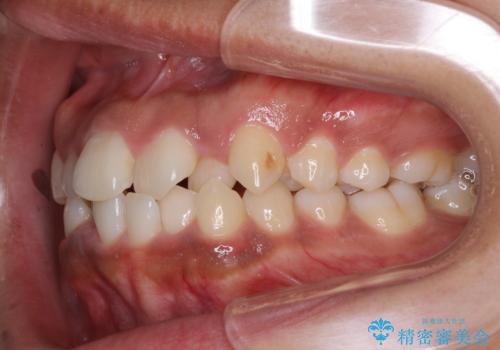

- 上下前歯の叢生を気にして来院された患者様です。

2年ほどインビザライン矯正を続けましたが、終了することができず、ワイヤーへ転換後は1年弱で終えることができました。